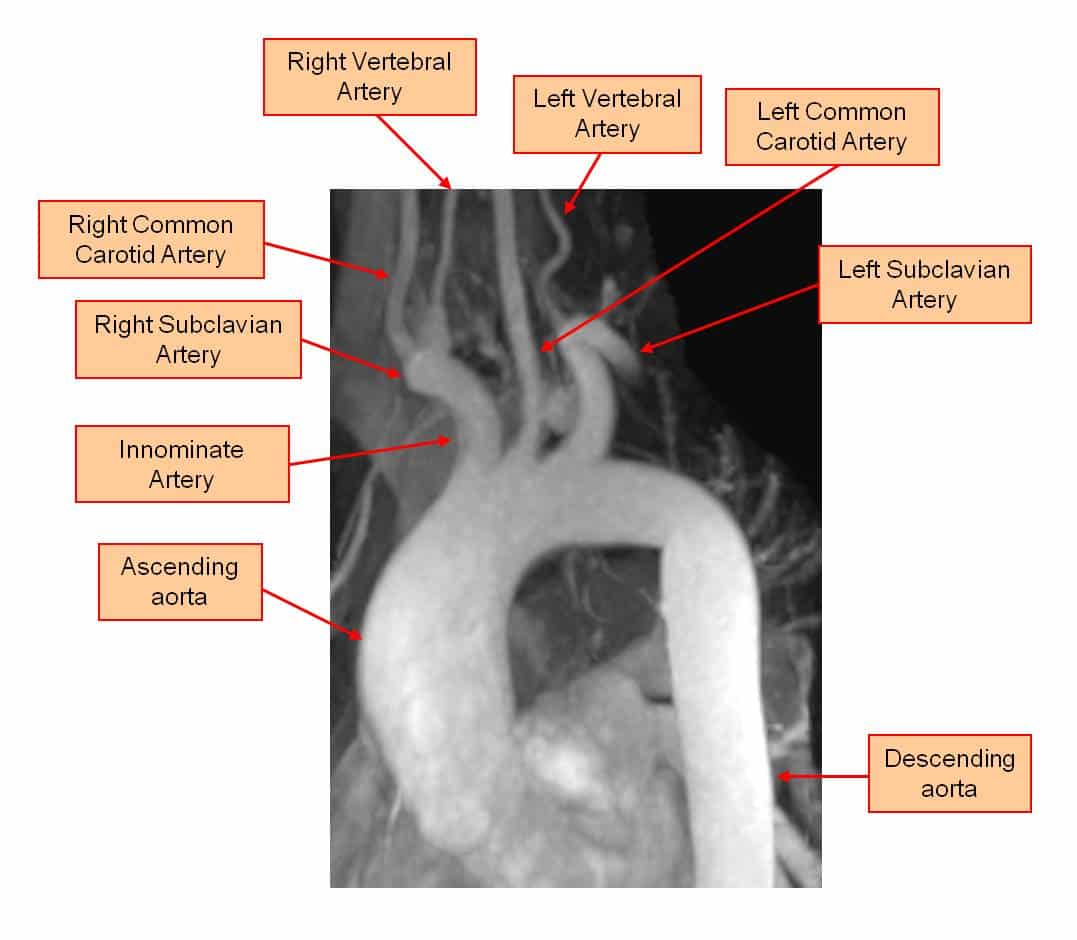

Anatomy of the aortic arch

Anatomy of the aortic arch. Notice the location of the vertebral arteries and the location of the subclavian arteries.